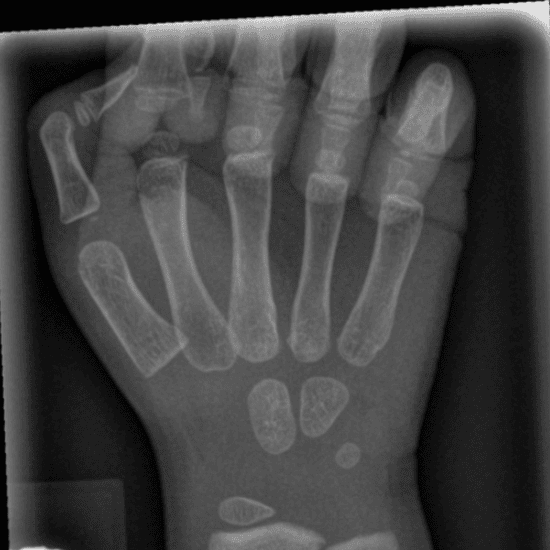

Simulates call by including subtle or difficult cases and some normals.

30 cases